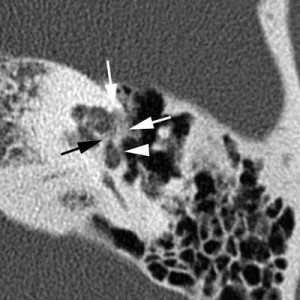

(Слева) При аксиальной КТ правой височной кости у молодого взрослого с прогрессирующей кондуктивной тугоухостью визуализируется типичная отоспонгиозная бляшка (фенестральный отосклероз) спереди от овального окна в области предполагаемой локализации щели перед окном.

(Справа) При корональной КТ правой височной кости у пациента со смешанной тугоухостью визуализируется рентгенонегативное «гало» вокруг улитки, обусловленное кохлеарным отосклерозом. Обратите также внимание на сопутствующий фенестральный отосклероз.

2. КТ при отосклерозе:

о Ранние изменения на КТ височных костей:

- Первичные изменения: рентгенонегативный фокус в области переднего края овального окна (ФОто)

- Поражение всех краев овального и круглого окон

- Возможно поражение слуховой капсулы внутреннего уха (КОто)

- Симптом двойного кольца или рентгенонегативное «гало», окружающее улитку, в случае тяжелого КОто

- При прогрессировании болезни возможно поражение любой части костного лабиринта, в том числе латеральной стенки наружного слухового канала

о Поздние, хронические (фаза заживления) изменения на КТ височных костей:

- ФОто: скопления вновь образованной костной ткани вдоль краев овального и круглого окон:

Бляшки могут приводить к окклюзии овального ± круглого окна

- КОто: смешанные рентгенонегативные-плотные очаги в костном лабиринте

(Справа) При аксиальной КТ левой височной кости визуализируется отоспонгиозная бляшка смешанной (склеротической и рентгено-негативной) структуры, приводящая к обструкции круглого окна. Отосклероз предрасполагает к невозможности протезирования стремечка и затрудняет кохлеарную имплантацию.